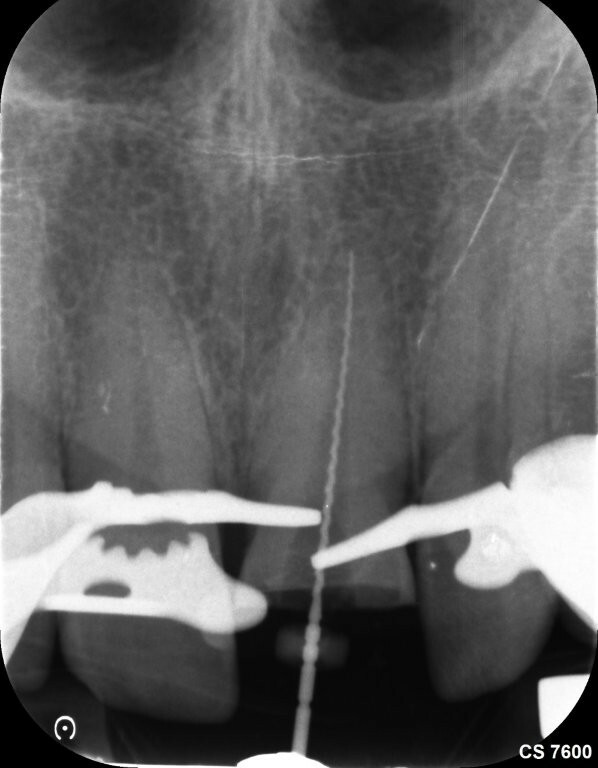

Das Zahnfragment hatte eine gute Passung auf den frakturierten Stumpf. So konnte im Vorfeld ein Silikonabdruck als Vorwall für den Kompositaufbau erstellt werden. Die endodontische Therapie sowie der Füllungsaufbau erfolgten ausschließlich unter dem hochauflösenden OP-Mikroskop (Zumax OMS2350). Die zu behandelnde Region wurde mit Ubistesin 1/200000 lokal betäubt. Anschließend wurde von 11 bis 22 ein Kofferdam angebracht. Der Zahn wurde mit einem konischen Diamanten trepaniert, die Trepanationsöffnung mit Gates-Glidden-Bohrern erweitert. Die Aufbereitung erfolgte mit dem Reciproc Blue System bis zur Größe 50.05.

Die Wurzelfüllung erfolgte in Continuus Wave Technik und Backfill in zwei Inkrementen mit

Guttapercha und AH Plus als Sealer. Anschließend wurden aufgrund der ovalen Kavität zwei Glasfaserstifte zur Stabilisation der Füllung eingebracht und mit Luxacore adhäsiv verklebt.